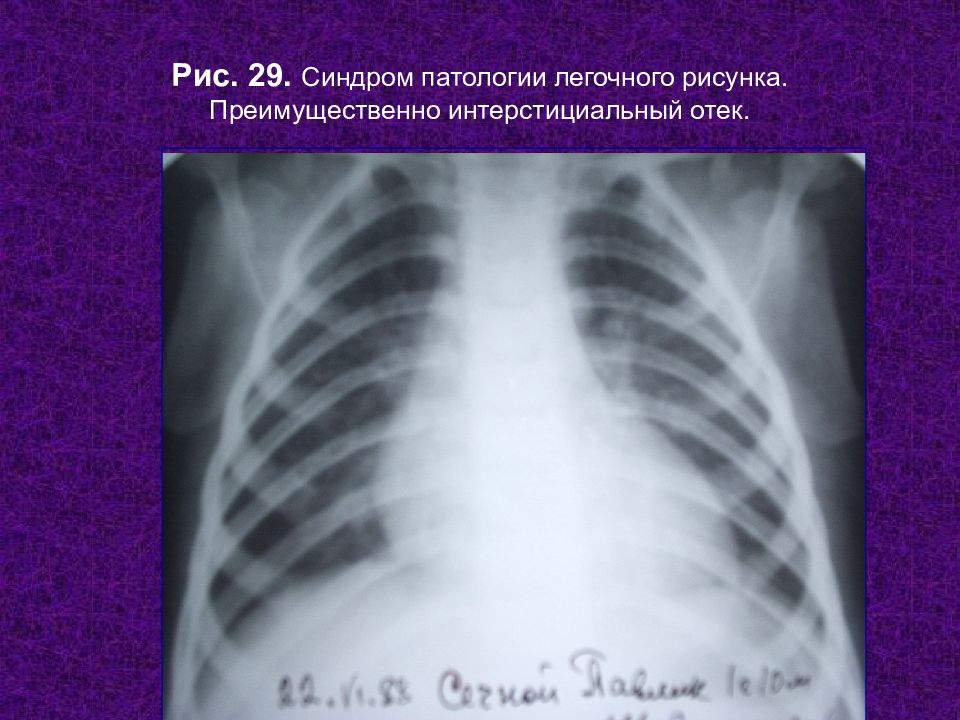

Рентгенологические изображения и синдромы патологии легких

Раздел: Кадры-подсказки